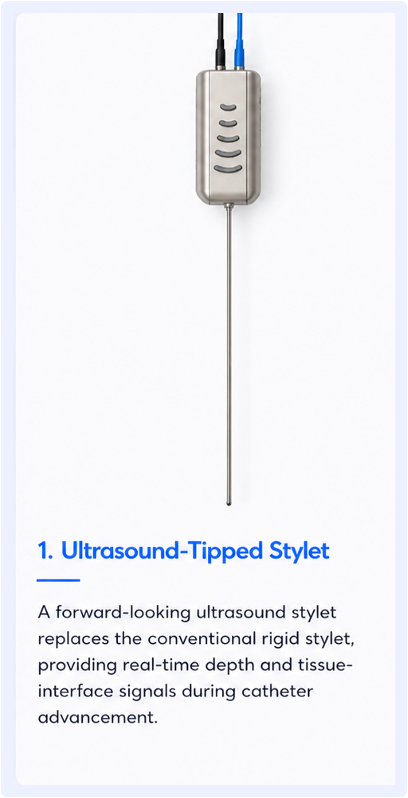

Our team is building the world’s first ultrasound and reconstruction algorithm capable of 3D imaging from an astounding 1.65mm diameter transducer. This provides neurosurgeons the tools they need for successful EVD placement in even the most challenging situations.

Three integrated technologies designed to make ventricular access visible in real time